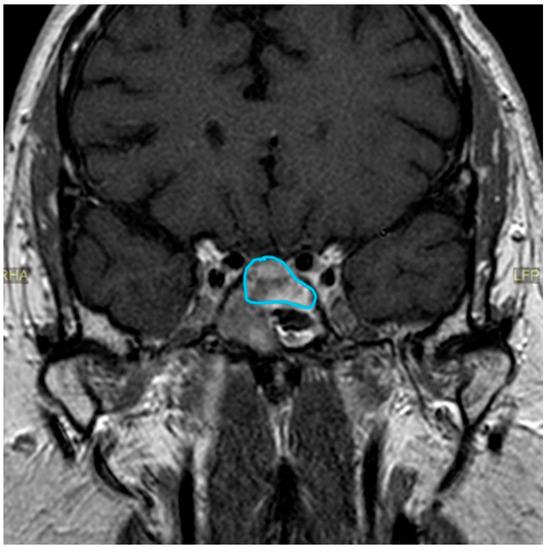

| Date | July 2018 | January 2019 | July 2019 | June 2020 | October 2020 | December 2020 | June 2021 |

|---|---|---|---|---|---|---|---|

| Prolactin (ng/mL) | 22.1 | 27.6 | 71.2 | 681.9 | 0.4 | 1.8 | |

| MRI | Macroadenoma (20 × 20 × 18 mm) with signs of pituitary apoplexy. Invasion of the optic chiasm, hypothalamus, and the left cavernous sinus. | 5 × 2 mm nodular structure that could be related to remnant glandular tissue. Persistent left deviation of the pituitary stalk. | Tumor growth (16 × 14 × 11 mm). Significant compression of the optic nerve and the optic chiasm. | Discrete decrease in volume of the tumor (13 × 12 × 8 mm). No compression of the optic nerve and the chiasm. | Volume reduction (13 × 10 × 6 mm). The structure is no longer in contact with the gyrus rectus and the subcallosal area. | ||

| Treatment | First surgical procedure | Second surgical procedure | Cabergoline started |